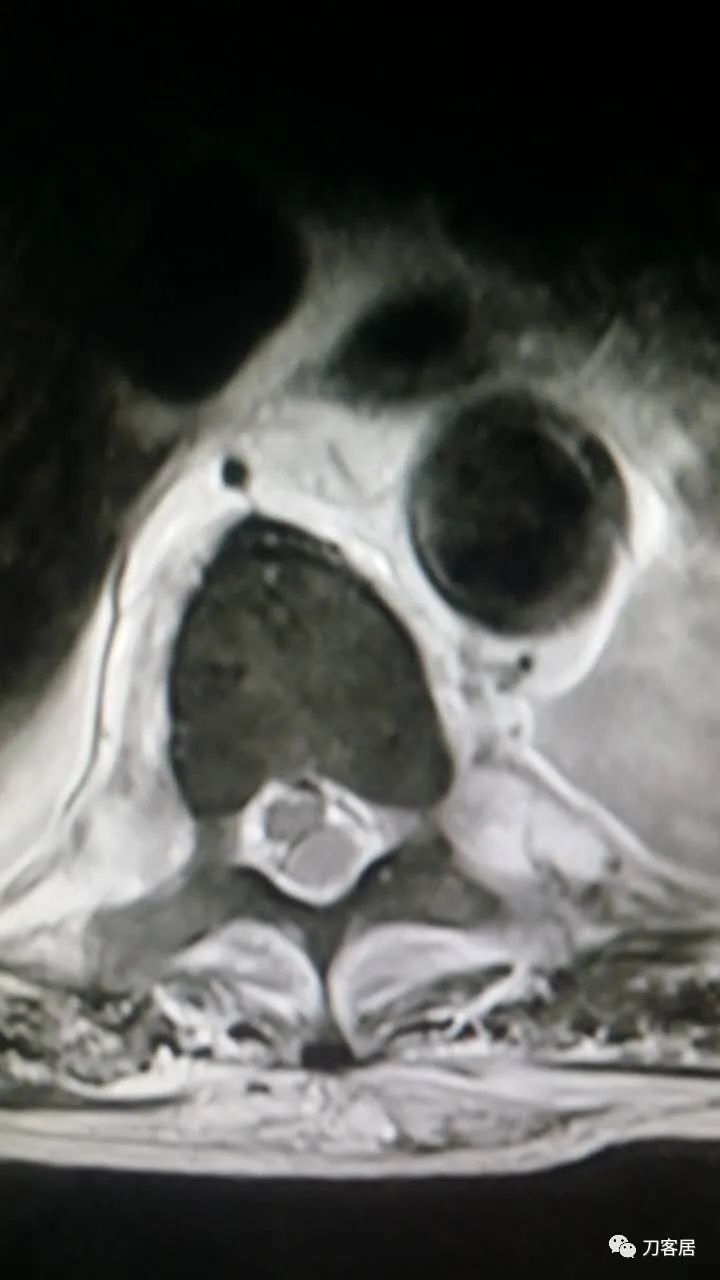

加注图10: 腰1-2椎管内后方可见梭形占位信号改变。

加注图11. 腰1-2椎管内后方可见梭形占位信号改变。